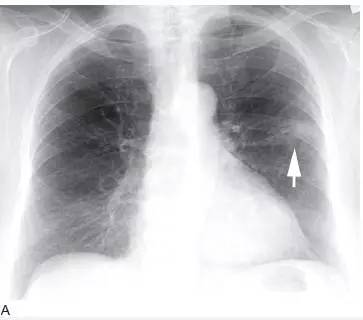

图7 弥漫性细支气管肺泡癌

A. 胸片显示右肺基底部的实变( 箭头);

B.5mm 层厚的CT 显示多个区域的实变,含有空气支气管征,多发的边界不清的结节,这些结节呈小叶中央分布,代表气腔或腺泡结节,在弥漫性细支气管肺泡癌中很常见